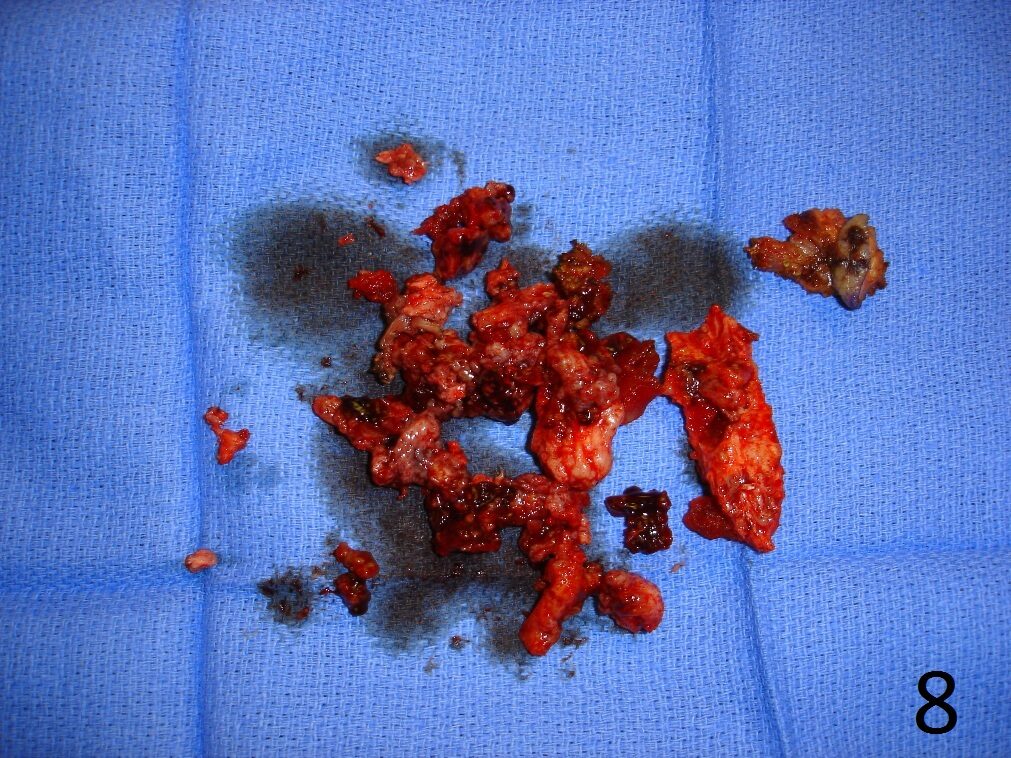

TREATMENT (Fig. 6-12)

Fig. 6

Fig. 7

Fig. 8

Fig. 9

Fig. 10

Fig. 11

Fig. 12

Fig. 6-12: Intraoperative photograph of the lesion (Fig. 6) and steps of the treatment (Fig. 7-12), excision, cryosurgery, gross specimen and cemented internal fixation